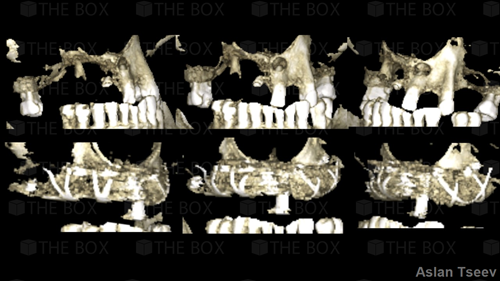

Infra bony defect one wall defect follow up 18 months show regeneration of buccal bone and interdental defect utilizing allograft bone substitute